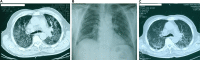

Intravesical administration of BCG is a relatively simple procedure used successfully in the treatment of superficial transitional cell carcinoma of the urinary bladder. It is usually well tolerated with few major side effects. The authors report the case of an 80-year-old man who presented with sepsis, jaundice, hepatic and pulmonary failure 10 days after his last BCG instillation therapy, that was attributed to concurrent granulomatous hepatitis and pneumonitis due to Mycobacterium bovis dissemination. In rare instances severe life-threatening complications occur in relation with BCG instillation immunotherapy that may involve multiple organs and have different presentations and require a high index of suspicion and clinical awareness in a wide range of medical specialties.